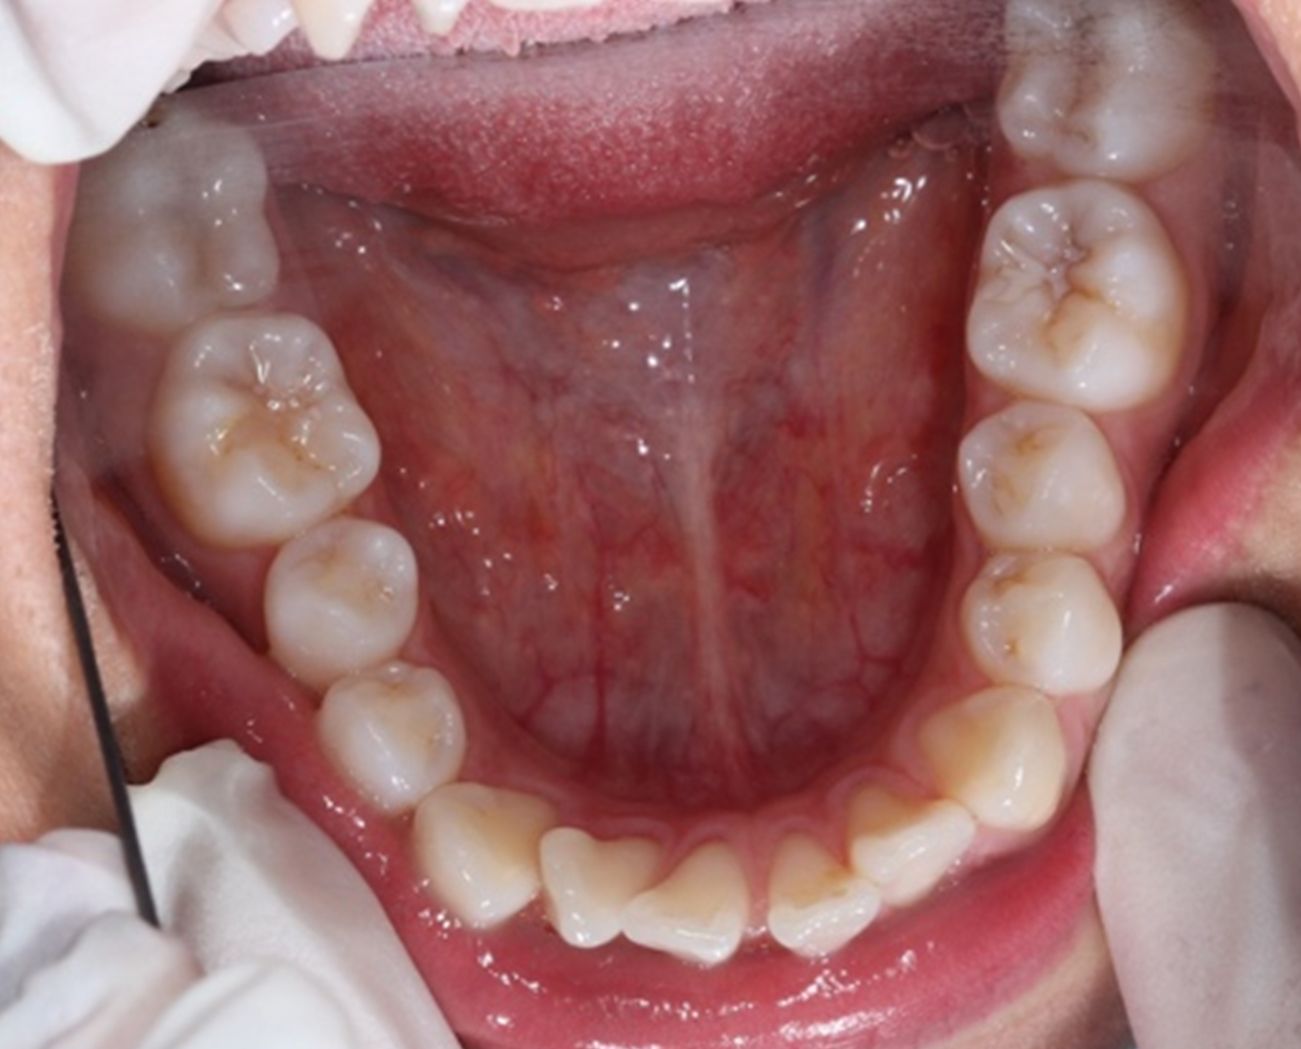

A continuación, mostramos el caso de una paciente adulta con clase II ósea y dentaria.

Con Ortodoncia Invisible, y gracias a la cooperación de la paciente, conseguimos este resultado y, lo más importante de todo, que la paciente sonría sin complejos.